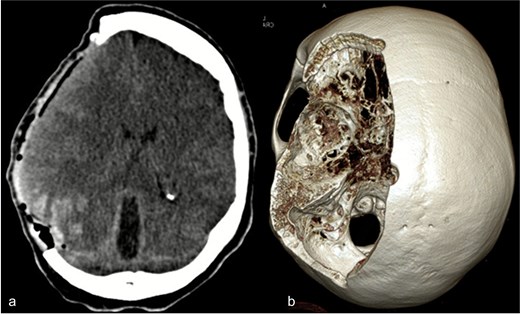

Due to elevated intracranial pressure caused by subdural and subarachnoid hemorrhage, an osteoclastic craniotomy was performed to evacuate the hematoma and relieve pressure (Fig. 2a and b). A large volume of blood was released during trepanation, necessitating intraoperative blood transfusion. Injury to the superior sagittal sinus during the procedure resulted in significant bleeding (Fig. 3), which was managed pharmacologically with the administration of clotting agents. The excised bone flap was sent for histological analysis, which was negative for bacterial infection.

(a) Axial CT image after osteoclastic craniotomy and (b) in the 3D reconstruction representation of the large bone defect.